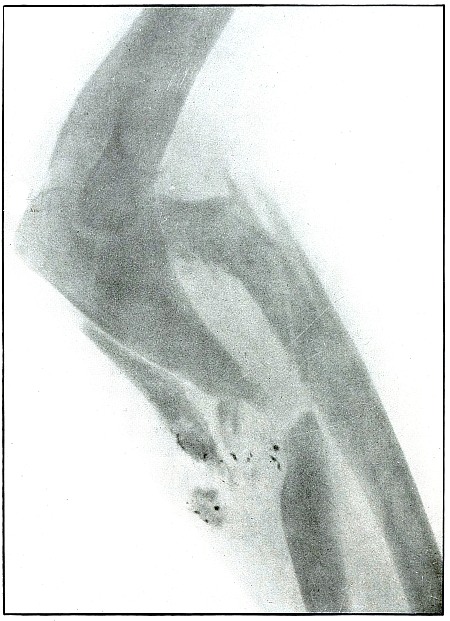

Plate 17.

[Pg 45]

Rifle—Plate 17.

UPPER EXTREMITY.

Gunshot Fracture of the Elbow.

The bullet in transverse course and high velocity through both bones

of the forearm struck the head of the radius, thus starting several

splitting lines of fracture and separating large fragments. Smaller

fragments which received some of the energy of the missile have been

carried along with it in turn, striking the ulna and carrying away

smaller fragments from it and causing the laceration which marks the

wound of exit.

Such wounds, with laceration of soft parts and fragmentation of the

bone, are prone to infection, against which treatment is directed. The

indications to be met are much like those of the wound shown in plates

18 and 19. Excision or

immediate methods of bone repair are contraindicated by infection.

Results will depend upon the nature and extent of infection.

[Pg 46]

Plate 18.

[Pg 47]

Rifle—Plate 18.

UPPER EXTREMITY.

Gunshot Fracture of the Elbow,

without Injury to the Great Vessels and Nerves.

Wound of entrance, posterior to the external condyle.

Wound of exit, large laceration in front and above the internal condyle.

The wound is an example of the misnamed “explosive” action of a rifle

bullet. The force and direction of the missile, in high velocity,

split the bone into many fragments, and, transmitting its energy to

some of the fragments, carried them through the skin and caused the

large laceration at the point of exit by the simultaneous escape of

the bullet and fragments. The wound was so heavily infected, that a

cellulitis advanced to the shoulder and to the wrist to such extent

that the arm was marked by eminent surgical opinion for amputation.

Free incision, drainage, antisepsis and incidental removal of detached

fragments controlled the infection and brought about slow resolution.

After six months of careful treatment the wound was healed with an

ankylosed elbow with normal function of the forearm, except for

limited rotation.

Treatment indicated in such cases is always conservative. Infections

contraindicate any formal surgical interference. The dangers of

infection in such cases are to be risked to avoid amputation.

Results may be considered favorable even with elbow ankylosis.

[Pg 48]

Plate 19.

[Pg 49]

Rifle—Plate 19.

UPPER EXTREMITY.

Gunshot Fracture of the Elbow,

without Injury to the Great Vessels and Nerves.

This is a plate made of the same subject shown in plate 18, when convalescence was several weeks

farther advanced, as is indicated by the removal of fragments and

extensive callus formation.

Both radiographs were made after the apprehension of systemic

infection had passed; the second plate after an additional number of

fragments had been removed.

[Pg 50]

Plate 20.

[Pg 51]

Rifle—Plate 20.

UPPER EXTREMITY.

Gunshot Fracture of the Elbow.

Wound of entrance, posterior aspect of forearm internal to and below

the olecranon.

Wound of exit, external border over head of radius.

The course of the bullet was diagonally anteroposterior from within

outward, striking the posterior border of the upper end of the ulna

and passing through the head of the radius, carrying the fragments

of the latter before it and lacerating the wound of exit. The energy

of impact also fissured the upper end of the shaft of the ulna and

fractured the neck of the radius without detaching the large fragments.

This is the effect of a rifle bullet at short range, or possibly a

ricochet shot at mid range.

The emergency treatment is antiseptic dressing with splint

immobilization.

The subsequent treatment is conservative, whether the wound is clean

or infected. The course of treatment of such an infected wound might

extend from four to six months.

Note.—As the

soldier always escapes the burden of explanation when the wound of

entrance is anterior rather than posterior, it should be remembered

that the forearm may occupy positions in relation to the body which

exposes the anatomically posterior aspect of the forearm to missiles

directed toward the anterior surface of the body; and as the wounds of

the forearm herein presented are described in the anatomical position,

there is no justifiable impeachment of the soldier’s valor in an

inference that he was shot from behind when the wound of entrance

involves the posterior aspect of the forearm.

[Pg 52]